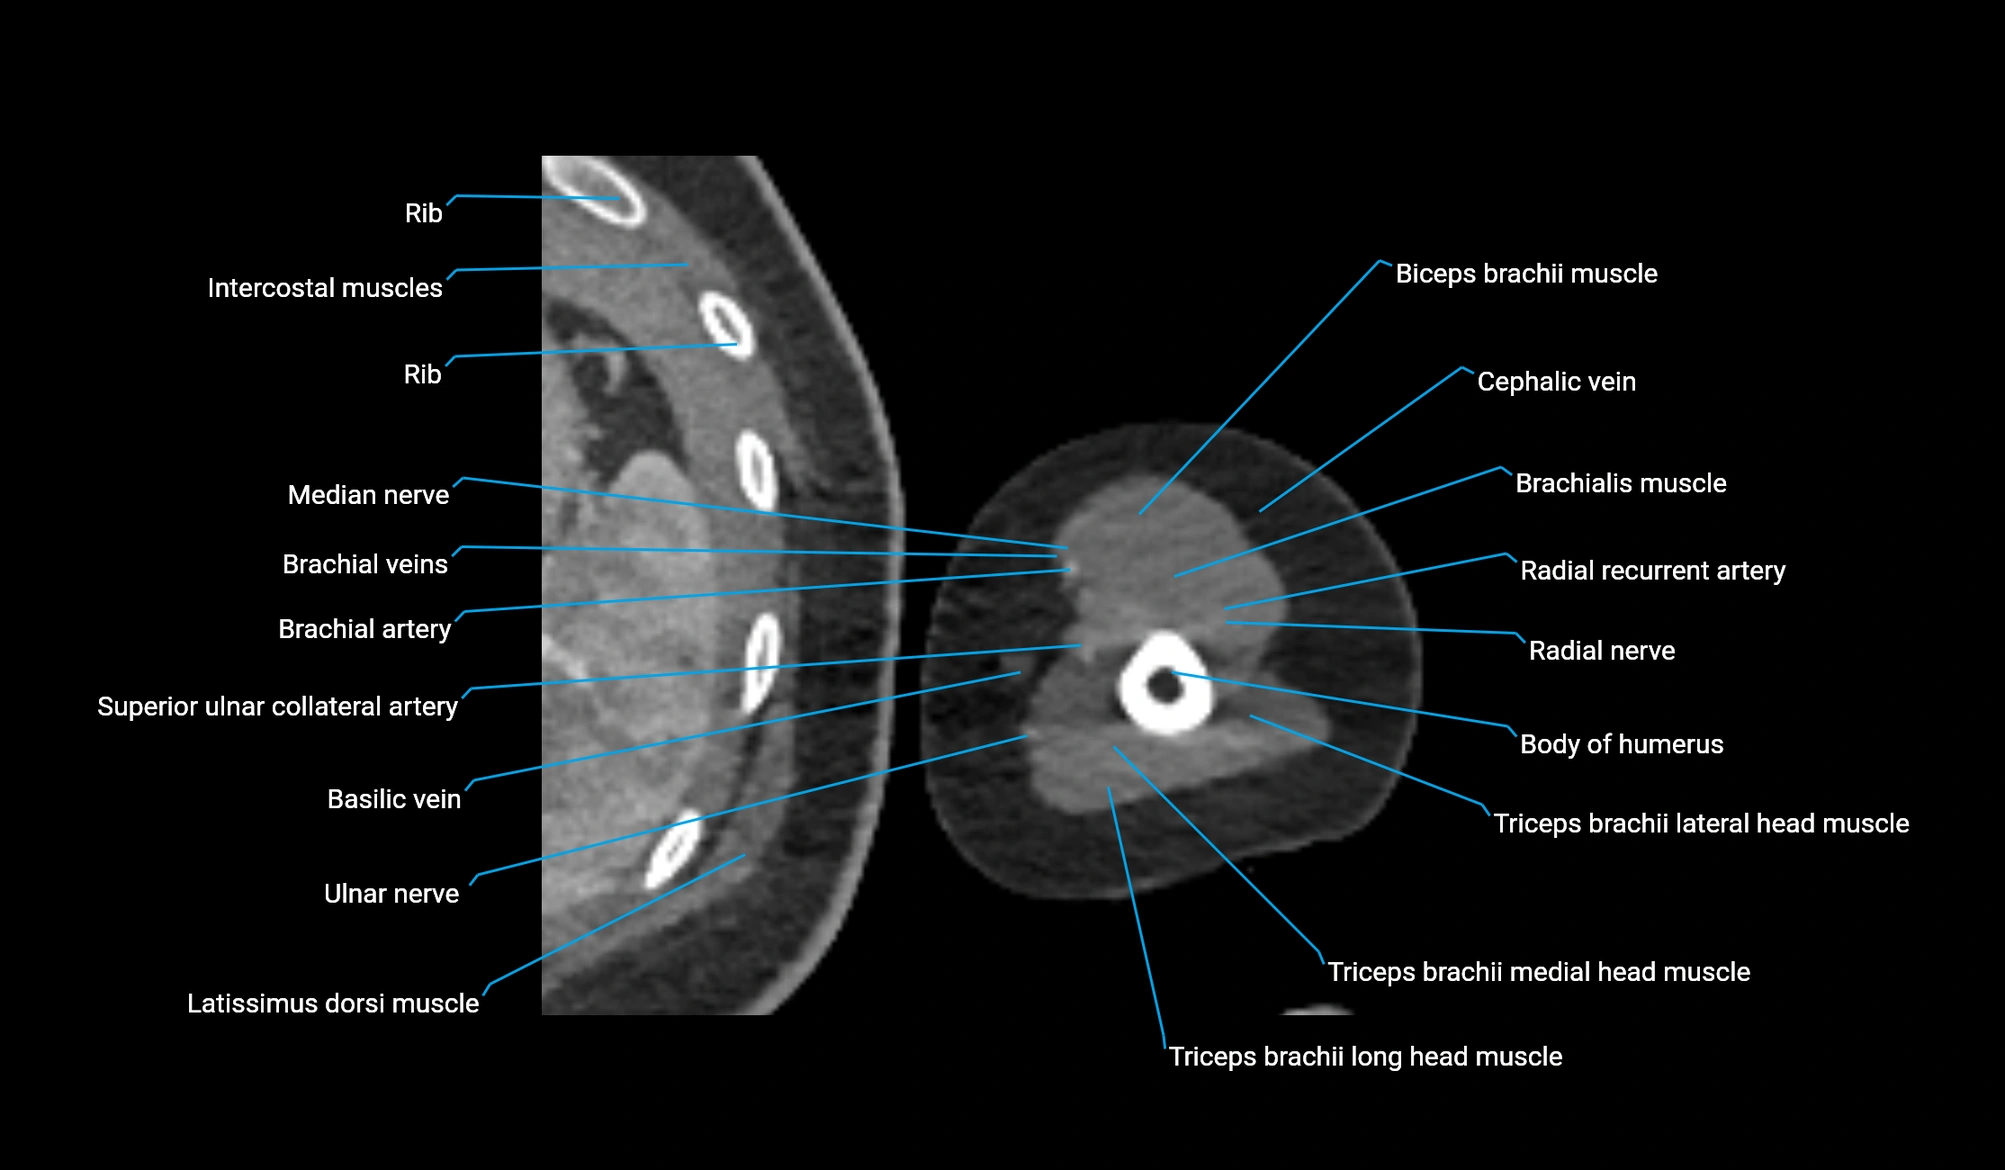

- Body of humerus

- Brachial artery

- Brachialis muscle

- Cephalic vein

- Long head of triceps brachii muscle

- Medial head of triceps brachii muscle

- Median nerve

- Radial nerve

- Radial recurrent artery

- Superior ulnar collateral artery

- Triceps brachii muscle

- Ulnar nerve